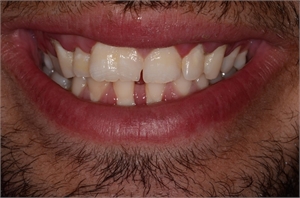

Tooth gemination in dentistry

Tooth gemination is also known as tooth twinning

Gemination of teeth appears when one tooth bud produces two teeth bonded together.

Gemination can be described as teeth ‘twinning’. In dental context, gemination refers to a developmental irregularity in which a single tooth germ divides resulting in a bifid crown on a single root, that is, two teeth develop together from a single tooth bud. The two parts of the double tooth will be exact images of each other. It is seen as a cleft crown on x-rays where the radiopaque enamel outlines the invagination.